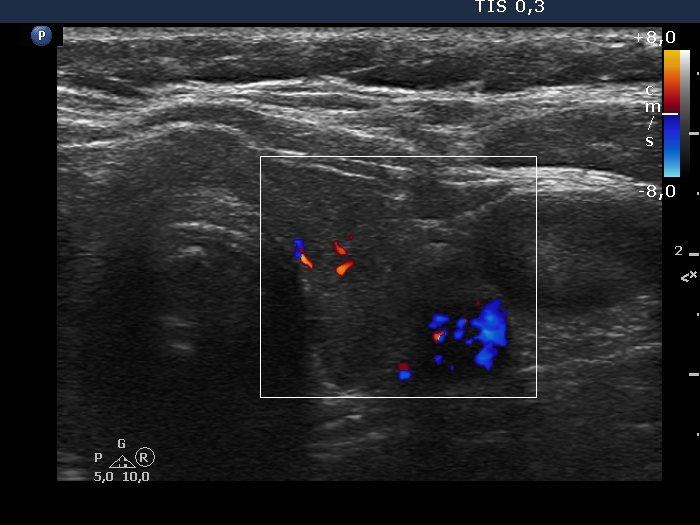

Lymphocytic thyroiditis - case 1442

Follow-up investigation 5 years after the first visit (ultrasonographic picture 6)

Left lobe, transverse scan, color Doppler mode. The vascularization is average.